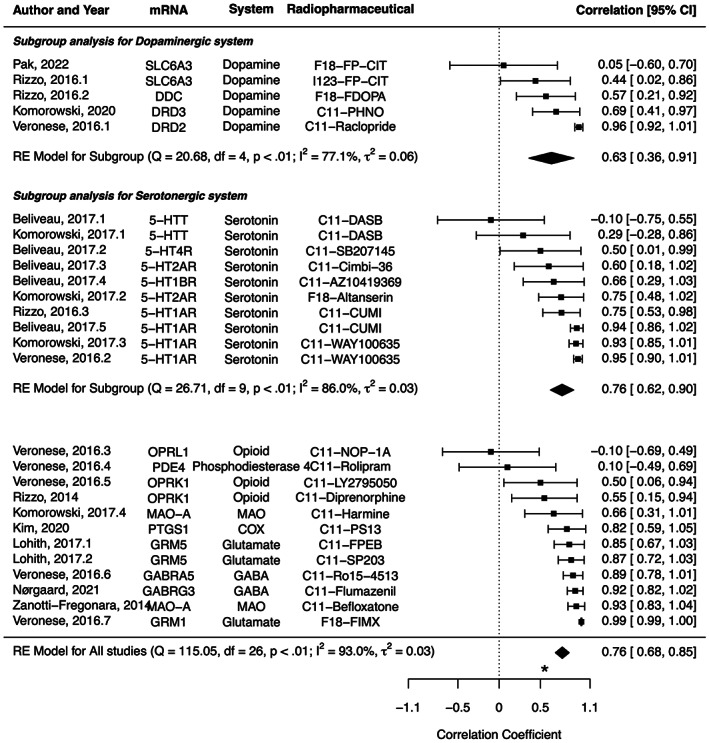

The characteristics of studies included in the meta‐analysis are summarized in Table 1. The correlation coefficient ranged from −.10 between 5‐HTT mRNA and C11‐DASB PET to .99 between GRM1 mRNA and F18‐FIMX PET, with a pooled effect of .76 (95% CI: .68–.85, I 2 = 93.0%) (Figure 5). In a subgroup analysis, the pooled correlation coefficients were .63 (.36–.91, I 2 = 77.1%) for dopaminergic system, and .76 (.62–.90, I 2 = 86.0%) for serotonergic system, without a significant difference (p = .4099).

Previously, the association of brain mRNA mappings of the Allen Human Brain Atlas with several PET‐derived protein expressions has been investigated, including serotonin receptors (Beliveau et al., ref. 2017; Komorowski et al., ref. 2017; Rizzo et al., ref. 2014), serotonin transporters (Beliveau et al., ref. 2017; Komorowski et al., ref. 2017), opioid receptors (Rizzo et al., ref. 2014), dopamine receptors (Komorowski et al., ref. 2020), and monoamine oxidase A (MAO‐A) (Komorowski et al., ref. 2017; Zanotti‐Fregonara et al., ref. 2014). The correlation coefficient ranged from −.10 between 5‐HTT mRNA and C11‐DASB PET to .99 between GRM1 mRNA and F18‐FIMX PET. We included one result with the strongest correlation between each radiopharmaceutical from single institution with one mRNA expression, as several studies report the association between a single radiopharmaceutical with several mRNAs. The presently observed correlations for CB1 (rho = .5067, p = .0337) was slightly weaker than the pooled result of this meta‐analysis. Even in the same neurotransmitter system, there was a difference in the associations between mRNA expression and protein expression according to the receptor or transporter. With the same gene expression of HTR1A mRNA from the Allen Human Brain Atlas, a wide range of correlation coefficients with protein expression has been shown; .75–.95, probably due to the characteristics of radiopharmaceuticals and ROIs included in each study. In addition, the majority of the studies included only a small number of subjects, typically <30. However, the moderate to strong correlation was observed between mRNA expression and protein expressions across multiple genes, showing the association of genes with protein levels of human brains. Recently, Hansen et al. reported the correlation between mRNA expression and multiple neurotransmitter receptors and transporters including CB1 receptor (Justine et al., ref. 2022). Poor spatial correspondences between mRNA expression and protein expression from PET scans were observed, except for 5 metabotropic receptors including CB1 receptor with a correlation coefficient of .66 (Justine et al., ref. 2022). However, their report did not include the relevant autoradiographic finding. In addition, subjects were scanned with the different radiopharmaceutical of C11‐OMAR with this study, making it difficult to compare with our result. There are a number of limitations that should be taken into account. First, F18‐FMPEP‐d2 PET scans were acquired from young males included in previous studies on feeding behavior and obesity (Kantonen, Karjalainen, et al., ref. 2021; Kantonen, Pekkarinen, et al., ref. 2021). Although no effect of age on CB1 receptor was reported in previous studies (Borgan et al., ref. 2019; Hirvonen et al., ref. 2012, ref. 2013), there is a difference in the age of participants between PET scan, autoradiography, and Allen Human Brain Atlas. The sample size of Allen Human Brain Atlas (n = 6) is too small to evaluate the age effect on mRNA expression and to give accurate result of the degree of correlation. In addition, the autoradiography study (Glass et al., ref. 1997) provides the average density of H3‐CP55940 binding in the adult human brain, without the density of each subject. Therefore, age could not be included as a covariate in this study. Second, while making the density atlas map of CB1 receptor, an area devoid of CB1 receptor would be estimated to have positive value of CB1 receptor density. A more accurate estimation for the linear conversion of V T to receptor density would be set the intercept = volume of non‐displaceable uptake. The linear conversion to receptor density will be erroneous for small V T. However, we used V T as the outcome measure to keep the results comparable with previous reports on the same CB1 receptor dataset (Kantonen, Karjalainen, et al., ref. 2021; Kantonen, Pekkarinen, et al., ref. 2021). Third, the method of calculation of mRNA expression from the Allen Human Brain Atlas and V T of F18‐FMPEP‐d2 PET might have an impact on the final results of this study. Further studies are needed to examine the association between protein expression based on multiple PET radioligands and gene expression with a uniform method.